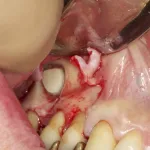

Your surgeon will cut the gum tissue where your back teeth used to be. The tissue is raised, exposing the bone. A small, oval window is opened in the bone. The membrane lining the sinus on the other side of the window separates your sinus from your jaw. This membrane is gently pushed up and away from your jaw.

Granules of bone-graft material are then packed into the space where the sinus was. The amount of bone used will vary, but usually several millimeters of bone is added above the jaw.

Once the bone is in place, the tissue is closed with stitches. Your implants will be placed four to nine months later. This allows time for the grafted material to mesh with your bone. The amount of time depends on the amount of bone needed.